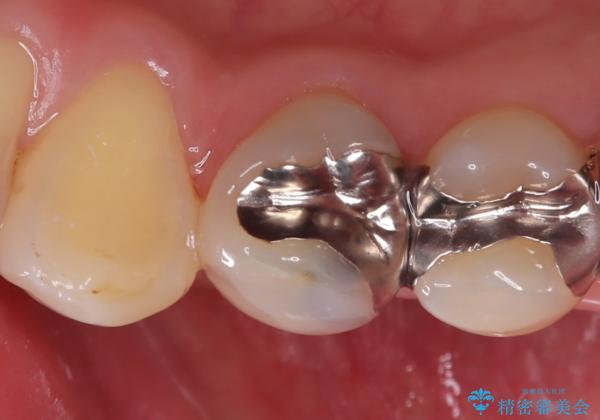

銀歯の下に虫歯 〈オールセラミッククラウン〉

- 初診時に金属の下に虫歯があることを指摘しました。もともとの詰め物の形と虫歯の大きさから被せものでの治療となりました。見た目、材質の説明をし、セラミッククラウンでの修復となりました。

メタルインレーが入っていたこと、う蝕が大きかったこと、頬側にHysに対してのCRがあったことを踏まえてクラウンでの修復を選択しました。